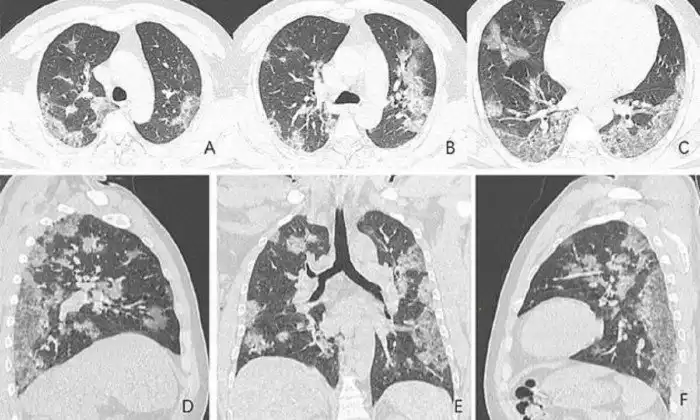

Рентгеновские снимки и томограммы легких 44-летнего пациента, умершего от коронавируса, были представлены китайскими врачами. Они дают подробную картину того, как вирус разрушает легкие человека. На снимках видны белые пятна в нижних отделах легких. Медики называют их "субплевральными уплотнениями по типу матового стекла". В этих областях воздушные пузырьки легких частично заполнены содержимым. Похожие поражения наблюдались также у пациентов с атипичной пневмонией и ближневосточным респираторным синдромом.

Умерший 44-летний мужчина из Китая жил в Ухани и работал на местном рынке морепродуктов, который, вероятно, стал источником нового вируса. Он был госпитализирован 25 декабря 2019 года после двух недель болезни. Врачи диагностировали у него пневмонию и острый респираторный дистресс синдром. Несмотря на лечение, он умер неделю спустя. Субплевральные уплотнения видны в его легких очень отчетливо. На снимках видно, как легкие со временем, от снимка А до снимка F, все сильнее заполняются жидкостью. Компьютерная томограмма легких 54-летней женщины, подхватившей коронавирус во время поездки в Ухань, показывает схожую картину.